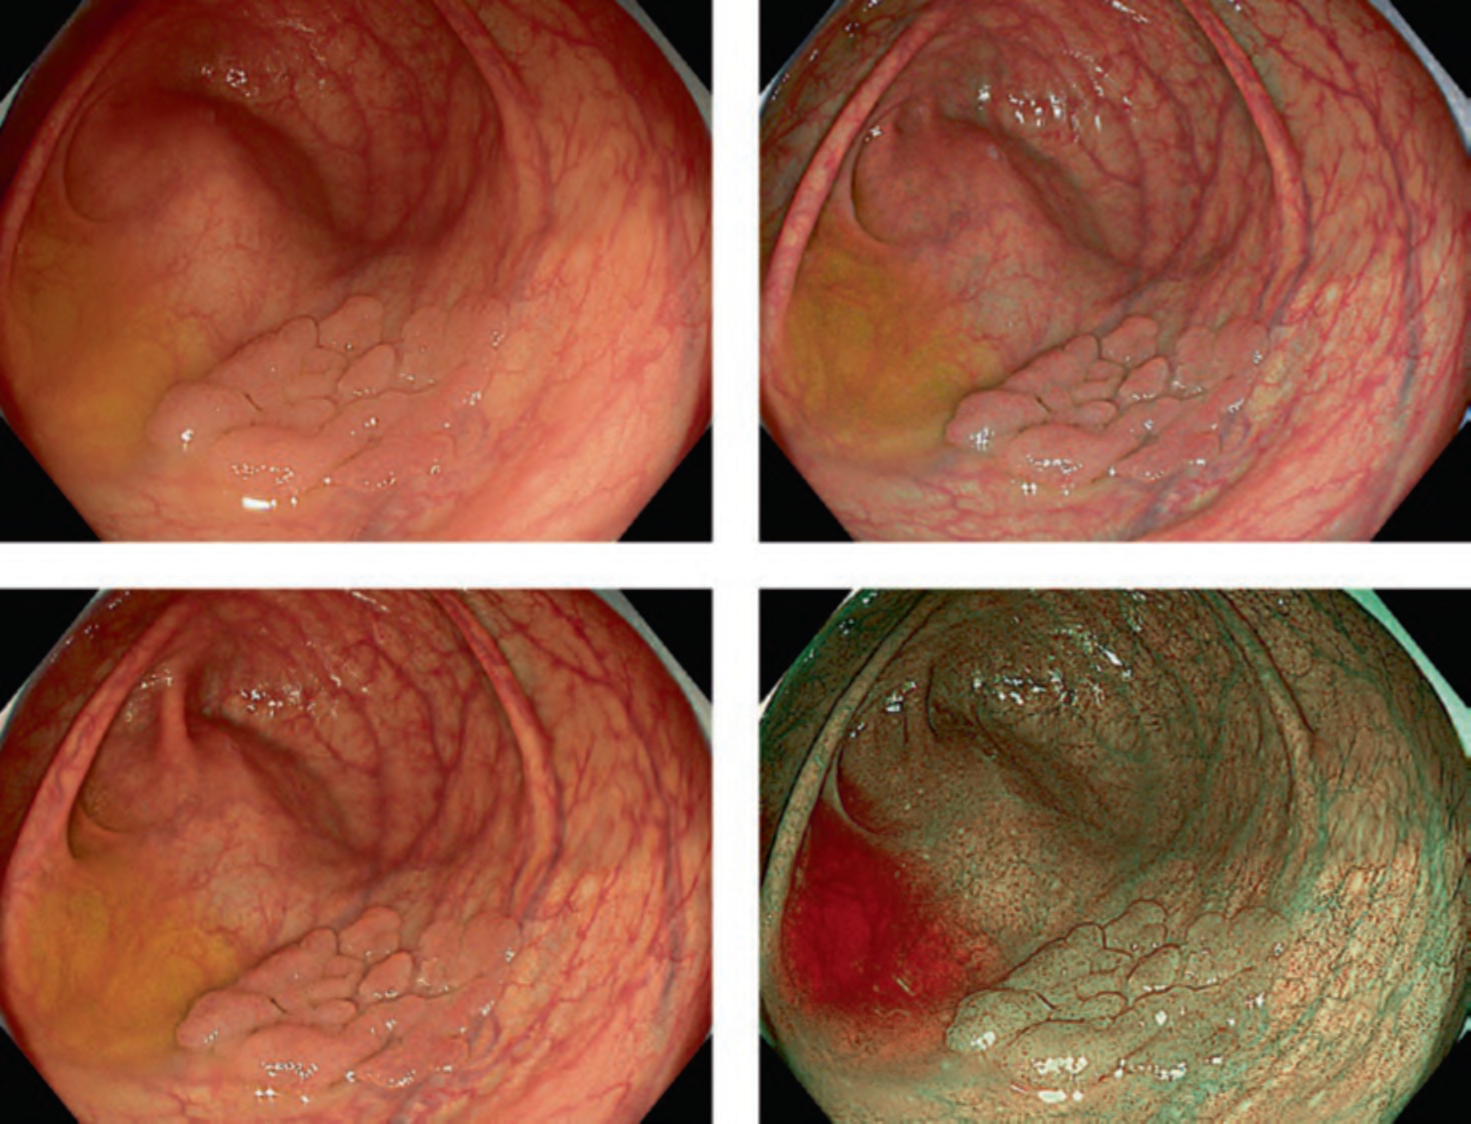

The LASEREO system (FUJIFILM Co., Tokyo, Japan) based on laser endoscopy was developed for advanced IEE, including WLI, BLI, and LCI. LCI using short-wavelength narrow band laser light combined with white laser light is a new technique that enhances differences in red coloration through digital processing [2]. This enables LCI to visualize red lesions better by enhancing their intensity relative to whitish lesions, which appear whiter. Recently, a controlled, multicenter trial with randomization using minimization has reported that LCI is more effective than WLI for detecting neoplastic lesions in the pharynx, esophagus, and stomach [3].

RDI is a type of novel IEE technology included in the EVIS X1 system launched by Olympus Co. in 2020. It is an imaging technique that enhances the contrast of deep tissue and blood vessels [4]. RDI has been reported to be useful for not only its initial development purpose, i.e., endoscopic hemostasis, but also other advanced interventions and even evaluation of inflammation activity. On the other hand, TXI developed by Olympus Co. is designed to enhance three image factors in WLI—texture, brightness, and color—to clearly define subtle tissue differences [5]. TXI is an innovative IEE that facilitates the adjustment of brightness and emphasizes surface irregularities and color differences in endoscopic images. As further data are accumulated, these new IEE technologies are expected to make a significant contribution to clinical practice.